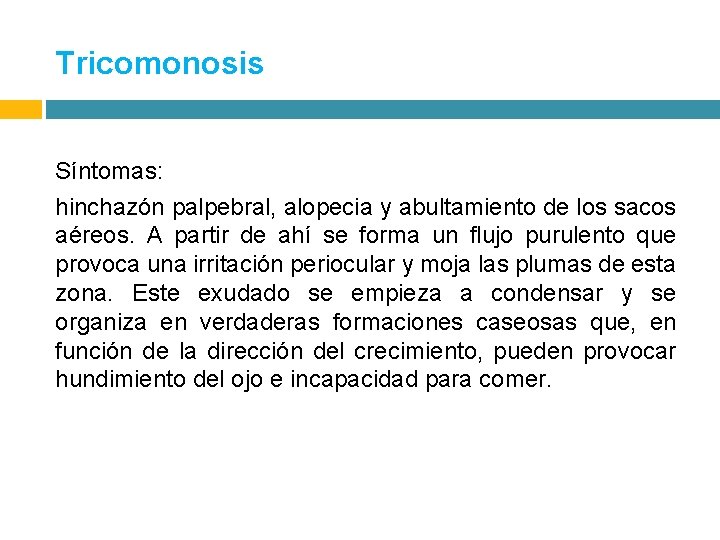

Tricomonosis Síntomas: hinchazón palpebral, alopecia y abultamiento de los sacos aéreos. A partir de ahí se forma un flujo purulento que provoca una irritación periocular y moja las plumas de esta zona. Este exudado se empieza a condensar y se organiza en verdaderas formaciones caseosas que, en función de la dirección del crecimiento, pueden provocar hundimiento del ojo e incapacidad para comer.